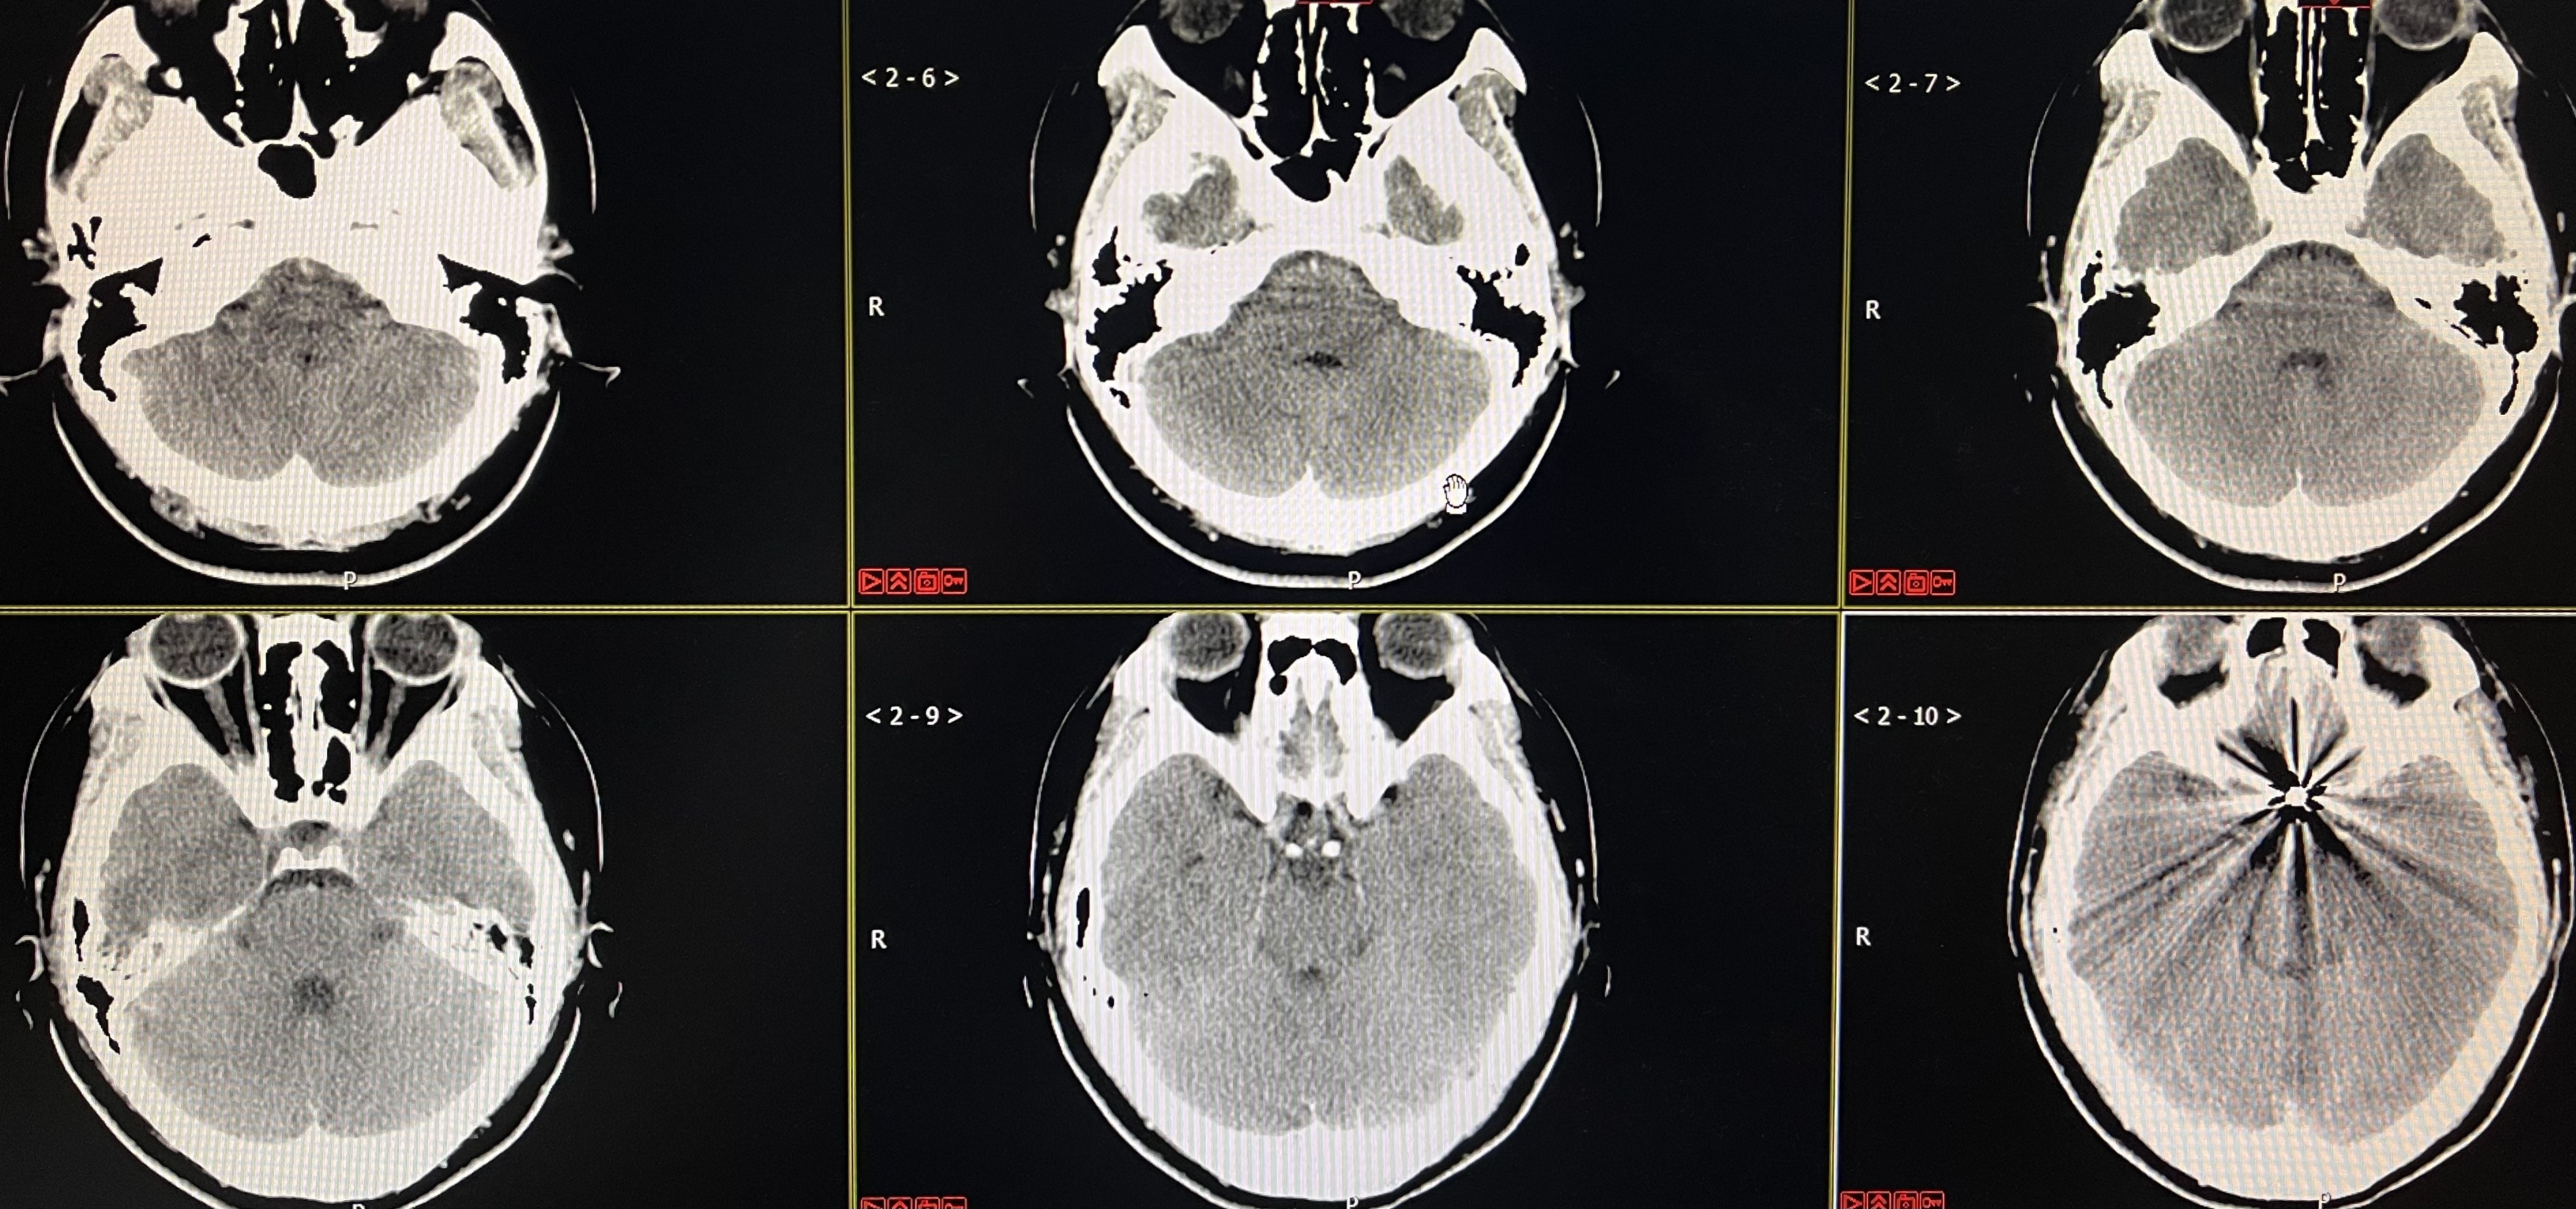

术后即刻CT

期待随访